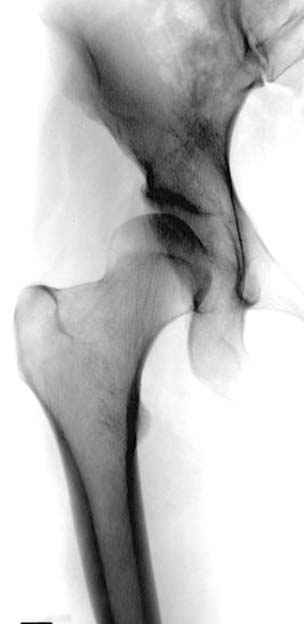

До операции #1

№ 1-3 до операции

№ 4-6 после операции при дисплазии тазобедренного

сустава